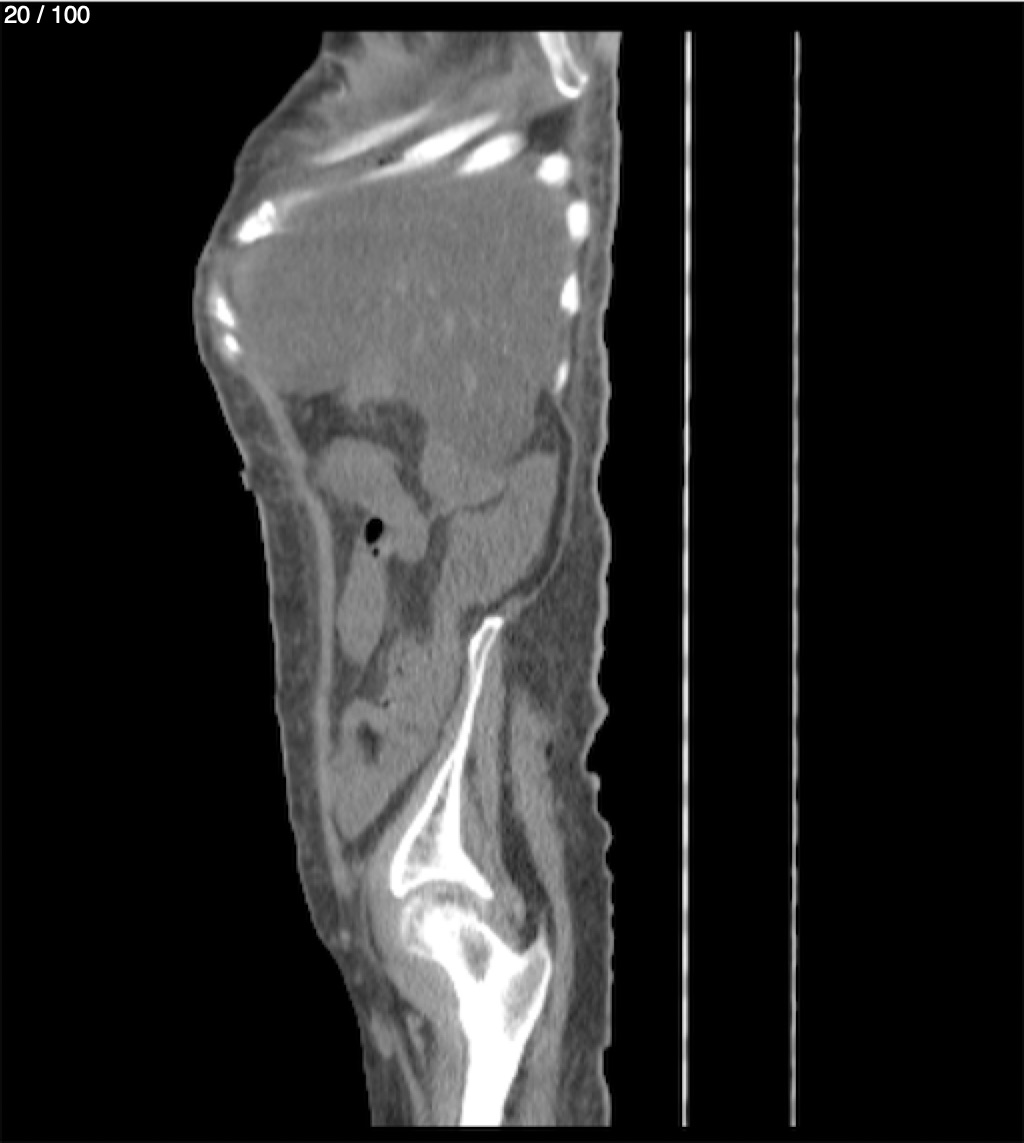

Hilda Geronimo Mendez 60A - T.C Abdomen Simple